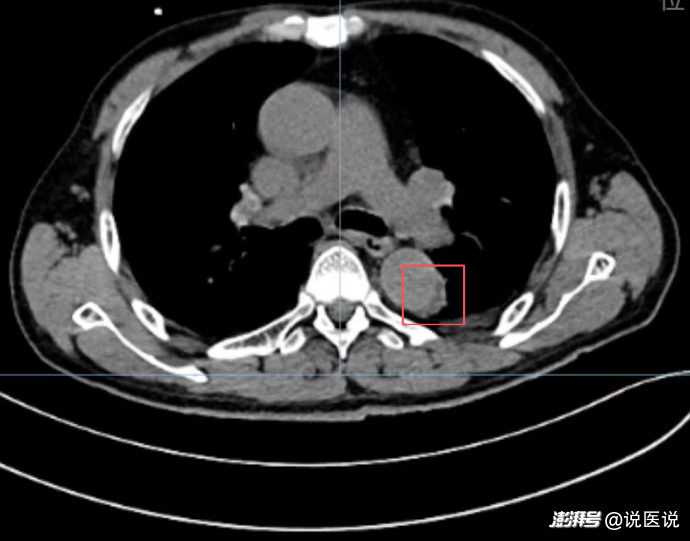

患者到院后,通過(guò)綠色通道迅速完成主動(dòng)脈CTA,結(jié)果明確提示“胸主動(dòng)脈壁間血腫”,與院前判斷高度一致。急診科醫(yī)生劉永琛立即啟動(dòng)結(jié)構(gòu)性心臟病科會(huì)診,患者被快速收治入院并接受手術(shù)。